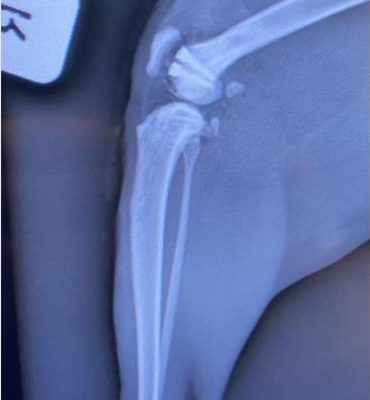

This resulted in a very severe and complicated fracture of her right femur involving the knee joint, according to Dr Adriaan Kitshoff of the University of Pretoria’s veterinary science faculty.

Bester said Theophylline underwent multiple surgeries to try and reconstruct her femur and knee joint.

The first of these surgeries included the insertion of numerous pins at various angles.

“This ensured that the alignment and length of the femur were salvaged,” she said.

Bester said after the femur bone has healed from the first surgery, Theophylline, unfortunately, developed an issue when the kneecap moved out of the groove of the knee joint.